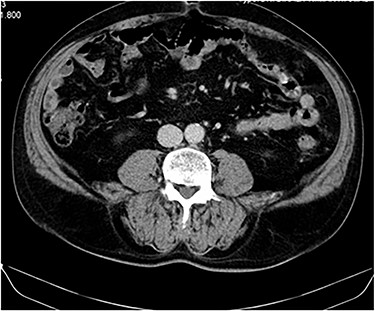

The staging computed tomography (CT) revealed a ‘nodular image with 48 × 57 × 44 mm, close to the anterior abdominal wall’ (Fig. 1) with active bleeding, two non-specific nodules in the left lung and five in the right lung, all infracentimetric.

CT images showing a nodular lesion with 48 × 57 × 44 mm, close to the anterior abdominal wall (yellow arrow).